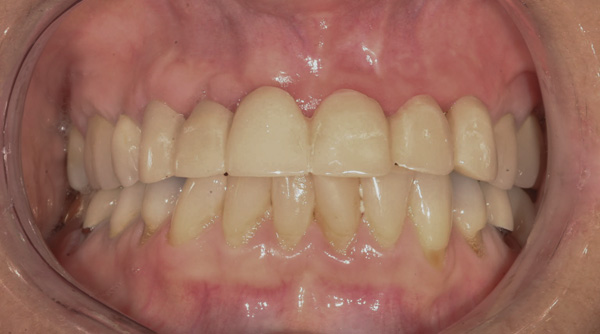

Background: The patient in this case presented with a failing dentition due to generalized severe periodontal disease with secondary endodontic lesions. She adamantly refused to wear removable transitional prostheses. Full maxillary and mandibular extractions were performed in the first phase of treatment. Not all implants could be placed in this initial phase due to the need for healing of certain grafted sites. The implants placed in this first phase were loaded with conical abutments and, in some cases, their angulated counterparts (Figure 16 and Figure 17). These stock titanium abutments were selected to avoid the need, as in Case 3, to change or remill the more costly custom abutments. They also have the advantage of making it unnecessary to use temporary cement near and around surgical sites, as they use occlusal screws only for retention.

Results: Stock titanium abutments were used until all tissue healing was achieved and the secondary implants had healed. Figure 18 shows the maxillary and mandibular custom abutments inserted. Figure 19 shows a close-up of the patient’s right side quadrants, depicting the final case 15 months after initial treatment began. Recession can be seen around units corresponding to teeth Nos. 5 and 6. In this case, the authors attempted to minimize recession susceptibility by employing stock temporary screw-retained abutments during healing phases throughout the initial stages of the treatment plan. Despite these efforts, recession still occurred in certain areas where the implants were labially placed. Since the photographs shown in this case were taken, an unsuccessful attempt was made by the patient’s surgeon to graft soft tissue around these sites with recession.

Figure 16 First-phase implants loaded with conical abutments and, in some cases, their angulated counterparts.

Figure 16

Figure 17 First-phase implants loaded with conical abutments and, in some cases, their angulated counterparts.

Figure 17

Figure 18 Custom abutments inserted.

Figure 18

Figure 19 Final result 15 months after initial treatment began, showing patient’s right side quadrants.

Figure 19